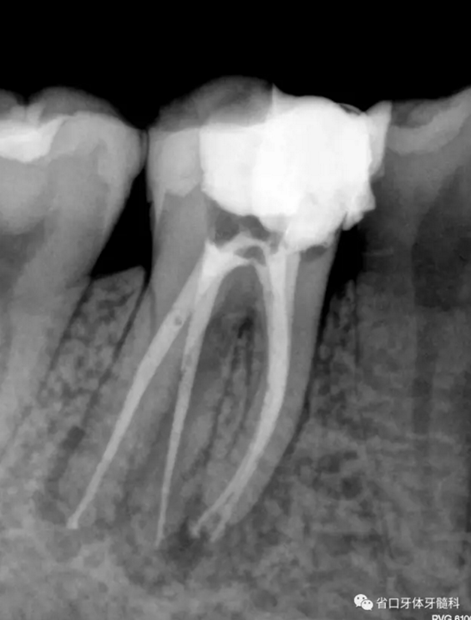

圖2 術后根充片